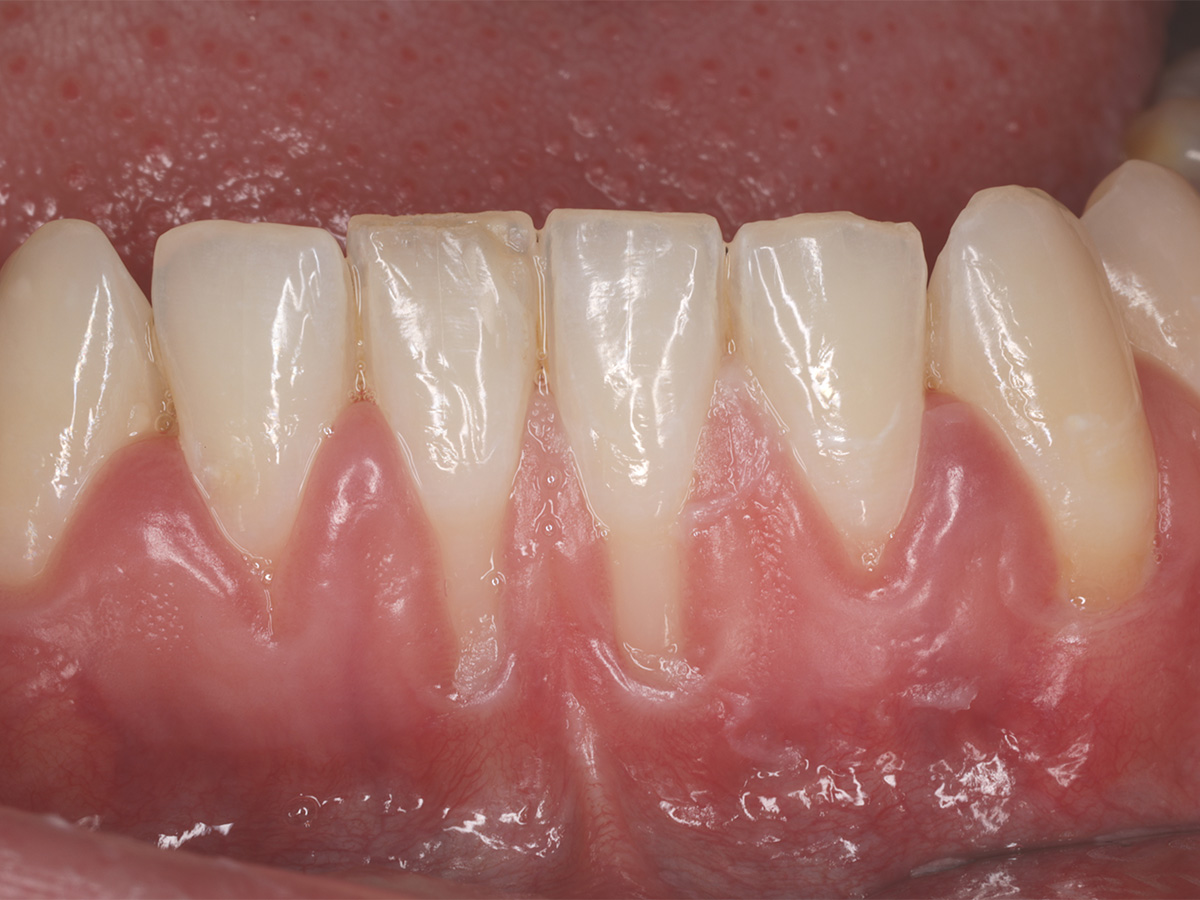

Abbildung 5

Klinische Situation 13 Monate nach Weichgewebsaugmentation.